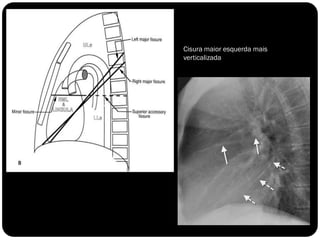

FISSURAS

Pulmões – lobos - fissuras

 Direito: 3 lobos (fissura oblíqua = maior e a horizontal =

menor)

 Esquerdo : 2 lobos (fissura oblíqua)

Vias aéreas

Traquéia       Fissuras interlobares: invaginações da pleura;

Brônquios

Bronquíolos

Alvéolos

Cisura maior esquerda mais

verticalizada

Pleura visceral